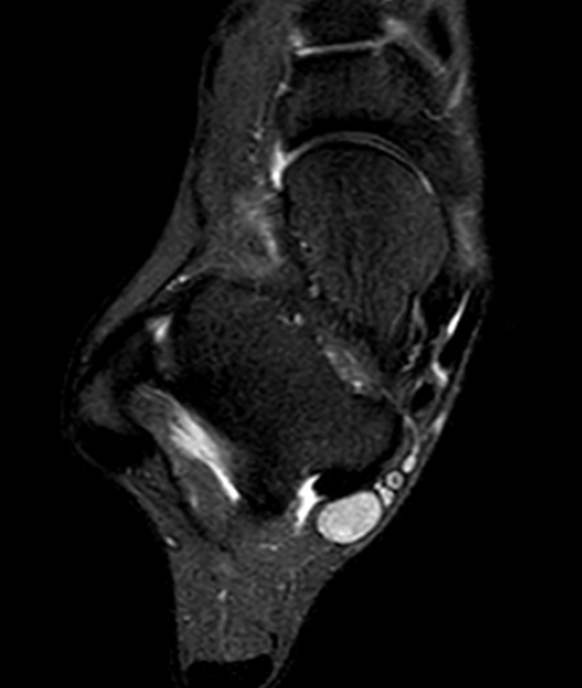

MRI - low signal on T1 and T2

PVNS anterolateral gutter ankle

PVNS with ankle joint / talus erosion